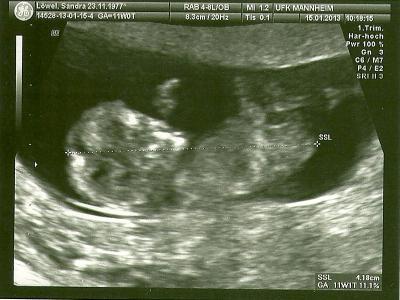

Ich hatte heute meinen Termin in der Klinik, mit dem Knirps ist alles gut, hat voll rumgezappelt, so daß der Doc meinte wir bekommen einen Tanzbären. Er hat nach Gesichtsmerkmalen geschaut und sich lange mit uns unterhalten, wegen gentischer Beratung, FWU und der gleichen, aber wir wollen nur auch den FUS zurückgreifen. Wir haben sogar ein 3D Bildchen bekommen und zum Schluß meinte er noch, der Kleine hat einen Zipfel, davon haben wir auch ein Bild bekommen. In 5 Wochen soll ich wieder kommen. LG ein paar Bildchen häng ich euch an.

Bild zu Heute Klinik - Forum für August - Mamis